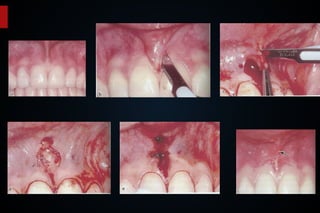

A paciente V. M., de 46 anos

Sistema de ancoragem utilizado no caso exposto.

Radiografias periapicais pré e pós- intrusão